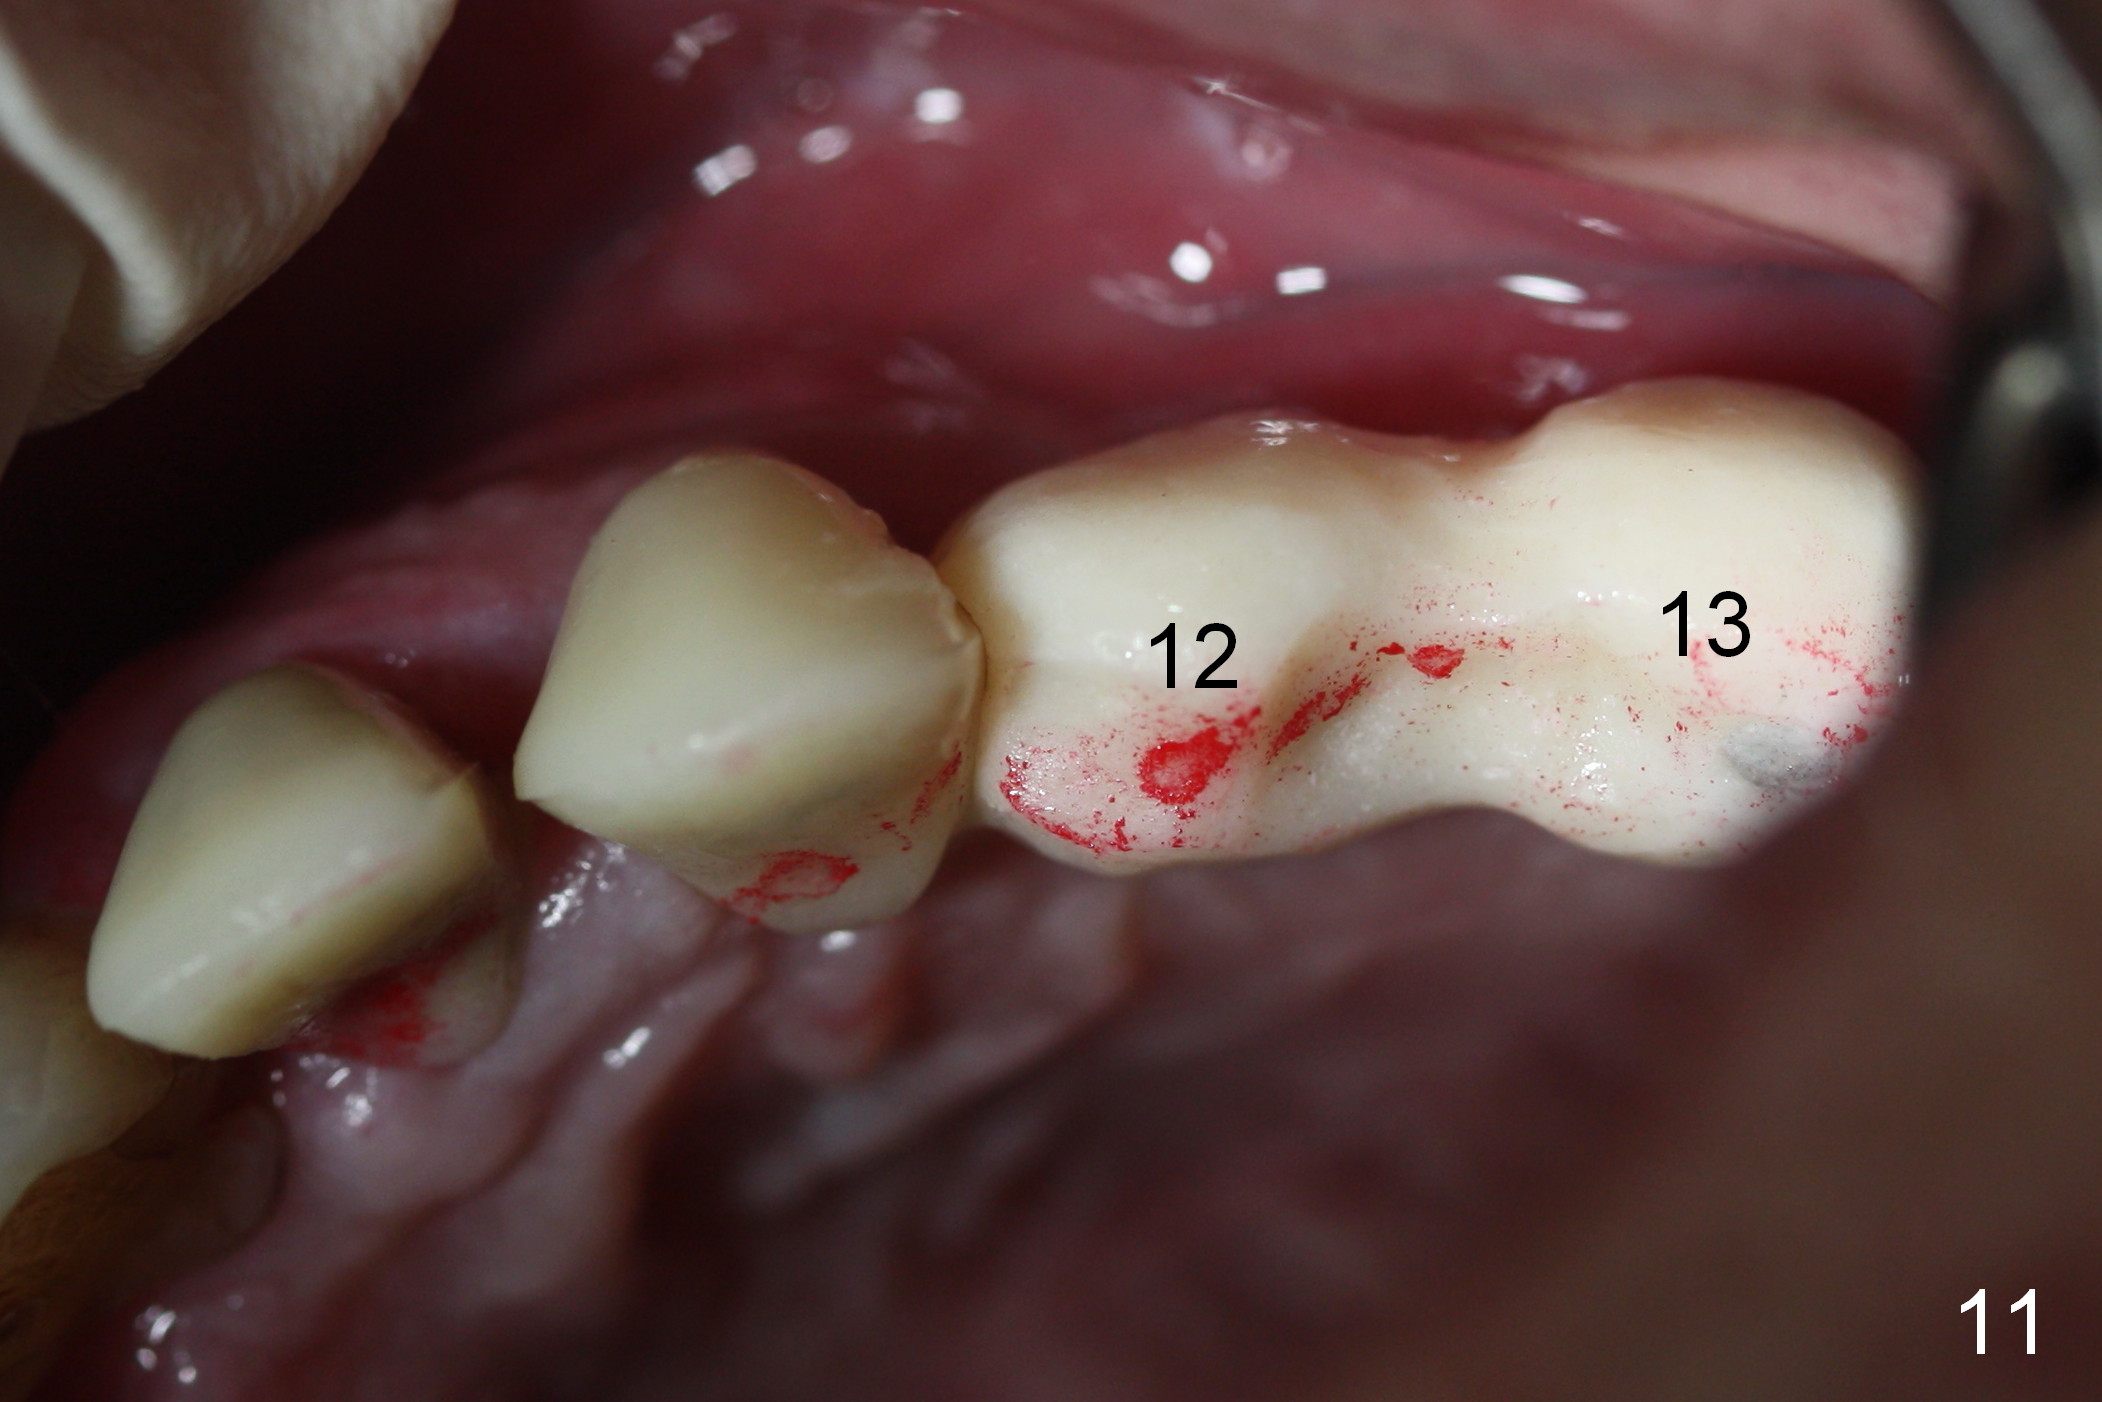

When the patient returns for implant placement (2nd visit after initial exam), he reveals that he is a dental phobic.  He requests placement of 4 implants in the upper left quadrant, instead of 2.  Narrow ridge is unexpected in the canine and premolar area (Fig.1).  Limited bone height at #13 (Fig.3 arrowheads: sinus floor) is found when initial drills are in place (Fig.2,3).  A 2-piece implant (4.5x17 mm tissue-level) is placed at #10 after extraction, while 1-piece implants are placed at 11 (3x17 mm (tissue-level, 15 °) and 12 and 13 (bone-level, 2.5x14, 12 mm, respectively; Fig.4,5).  In fact the 1 piece implant at #13 is not completely placed (Fig.5).  It is removed, the apical 3 threads are cut off (Fig.6 <, since a shorter implant was unavailable in the office) and the remaining implant is re-inserted.  The insertion torques of the 4 implants are ~ 60, ~ 35, < 35 and 15 Ncm, respectively.  After adjustment (Fig.7), immediate provisionals are fabricated at #10 and 11 (Fig.8, later splinted with composite), while perio dressing is applied around the implants at #12 and 13 and the provisionals at #10 and 11.  There is no nasal hemorrhage postop.  Although the perio dressing is loose 1 week postop (Fig.9), it is not removed.  When the upper lip fissure (Fig.9 <) heals, provisionals at #12 and 13 are planned to be splinted to the other two ones.  Two weeks postop, the upper lip fissure heals, the perio dressing dislodges and the implants at #12 and 13 are stable (Fig.10).  After abutment height adjustment, a splinted provisional is fabricated over these 2.5 mm 1-piece implants (Fig.11).